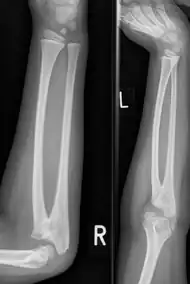

| Congenital radioulnar synostosis in a 7 year old boy | |

Radioulnar synostosis is a rare condition where there is an abnormal connection between the radius and ulna bones of the forearm.[1] This can be present at birth (congenital), when it is a result of a failure of the bones to form separately, or following an injury (post-traumatic).[2]

It typically causes restricted movement of the forearm, in particular rotation (pronation and supination), though is not usually painful unless it causes subluxation of the radial head.[1] It can be associated with dislocation of the radial head which leads to limited elbow extension.[2]

Diagnosis at birthday is best done using ultrasound technology. In younger children and adults diagnosis is done with x-ray machine at the radioulnar bones.